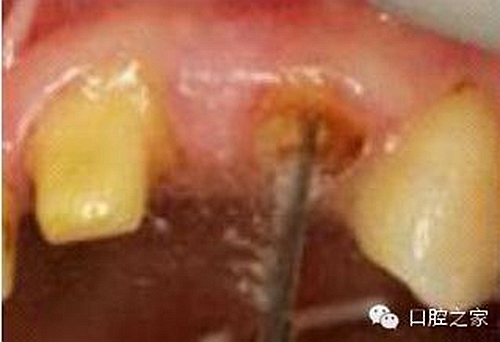

圖3:根管內(nèi)殘留物

圖4:超聲去除根管殘留物。

根管壁殘留物的存在直接影響著纖維樁的粘接和固位,是纖維樁脫落的主要原因之一。由于圓形的根管鉆和根管形態(tài)不完全一致,終鉆預(yù)備完成后大多情況下樁道側(cè)壁會有不同程度的牙膠和封閉劑等殘留物附著(圖 3)。因此,建議X線檢查根管預(yù)備情況,選用超聲潔牙機更換較細工作尖進入根管,徹底去除樁道根管壁上附著的殘留物(圖4)。使用根管銼去除殘留物時,很難清除干凈;禁止使用牙膠溶劑如丁克除、氯仿等有機溶劑去除殘留物,以免破壞根尖區(qū)牙膠的封閉,或有機溶劑粘附于根管壁形成蠟?zāi)ざ绊懻辰印?#pages##